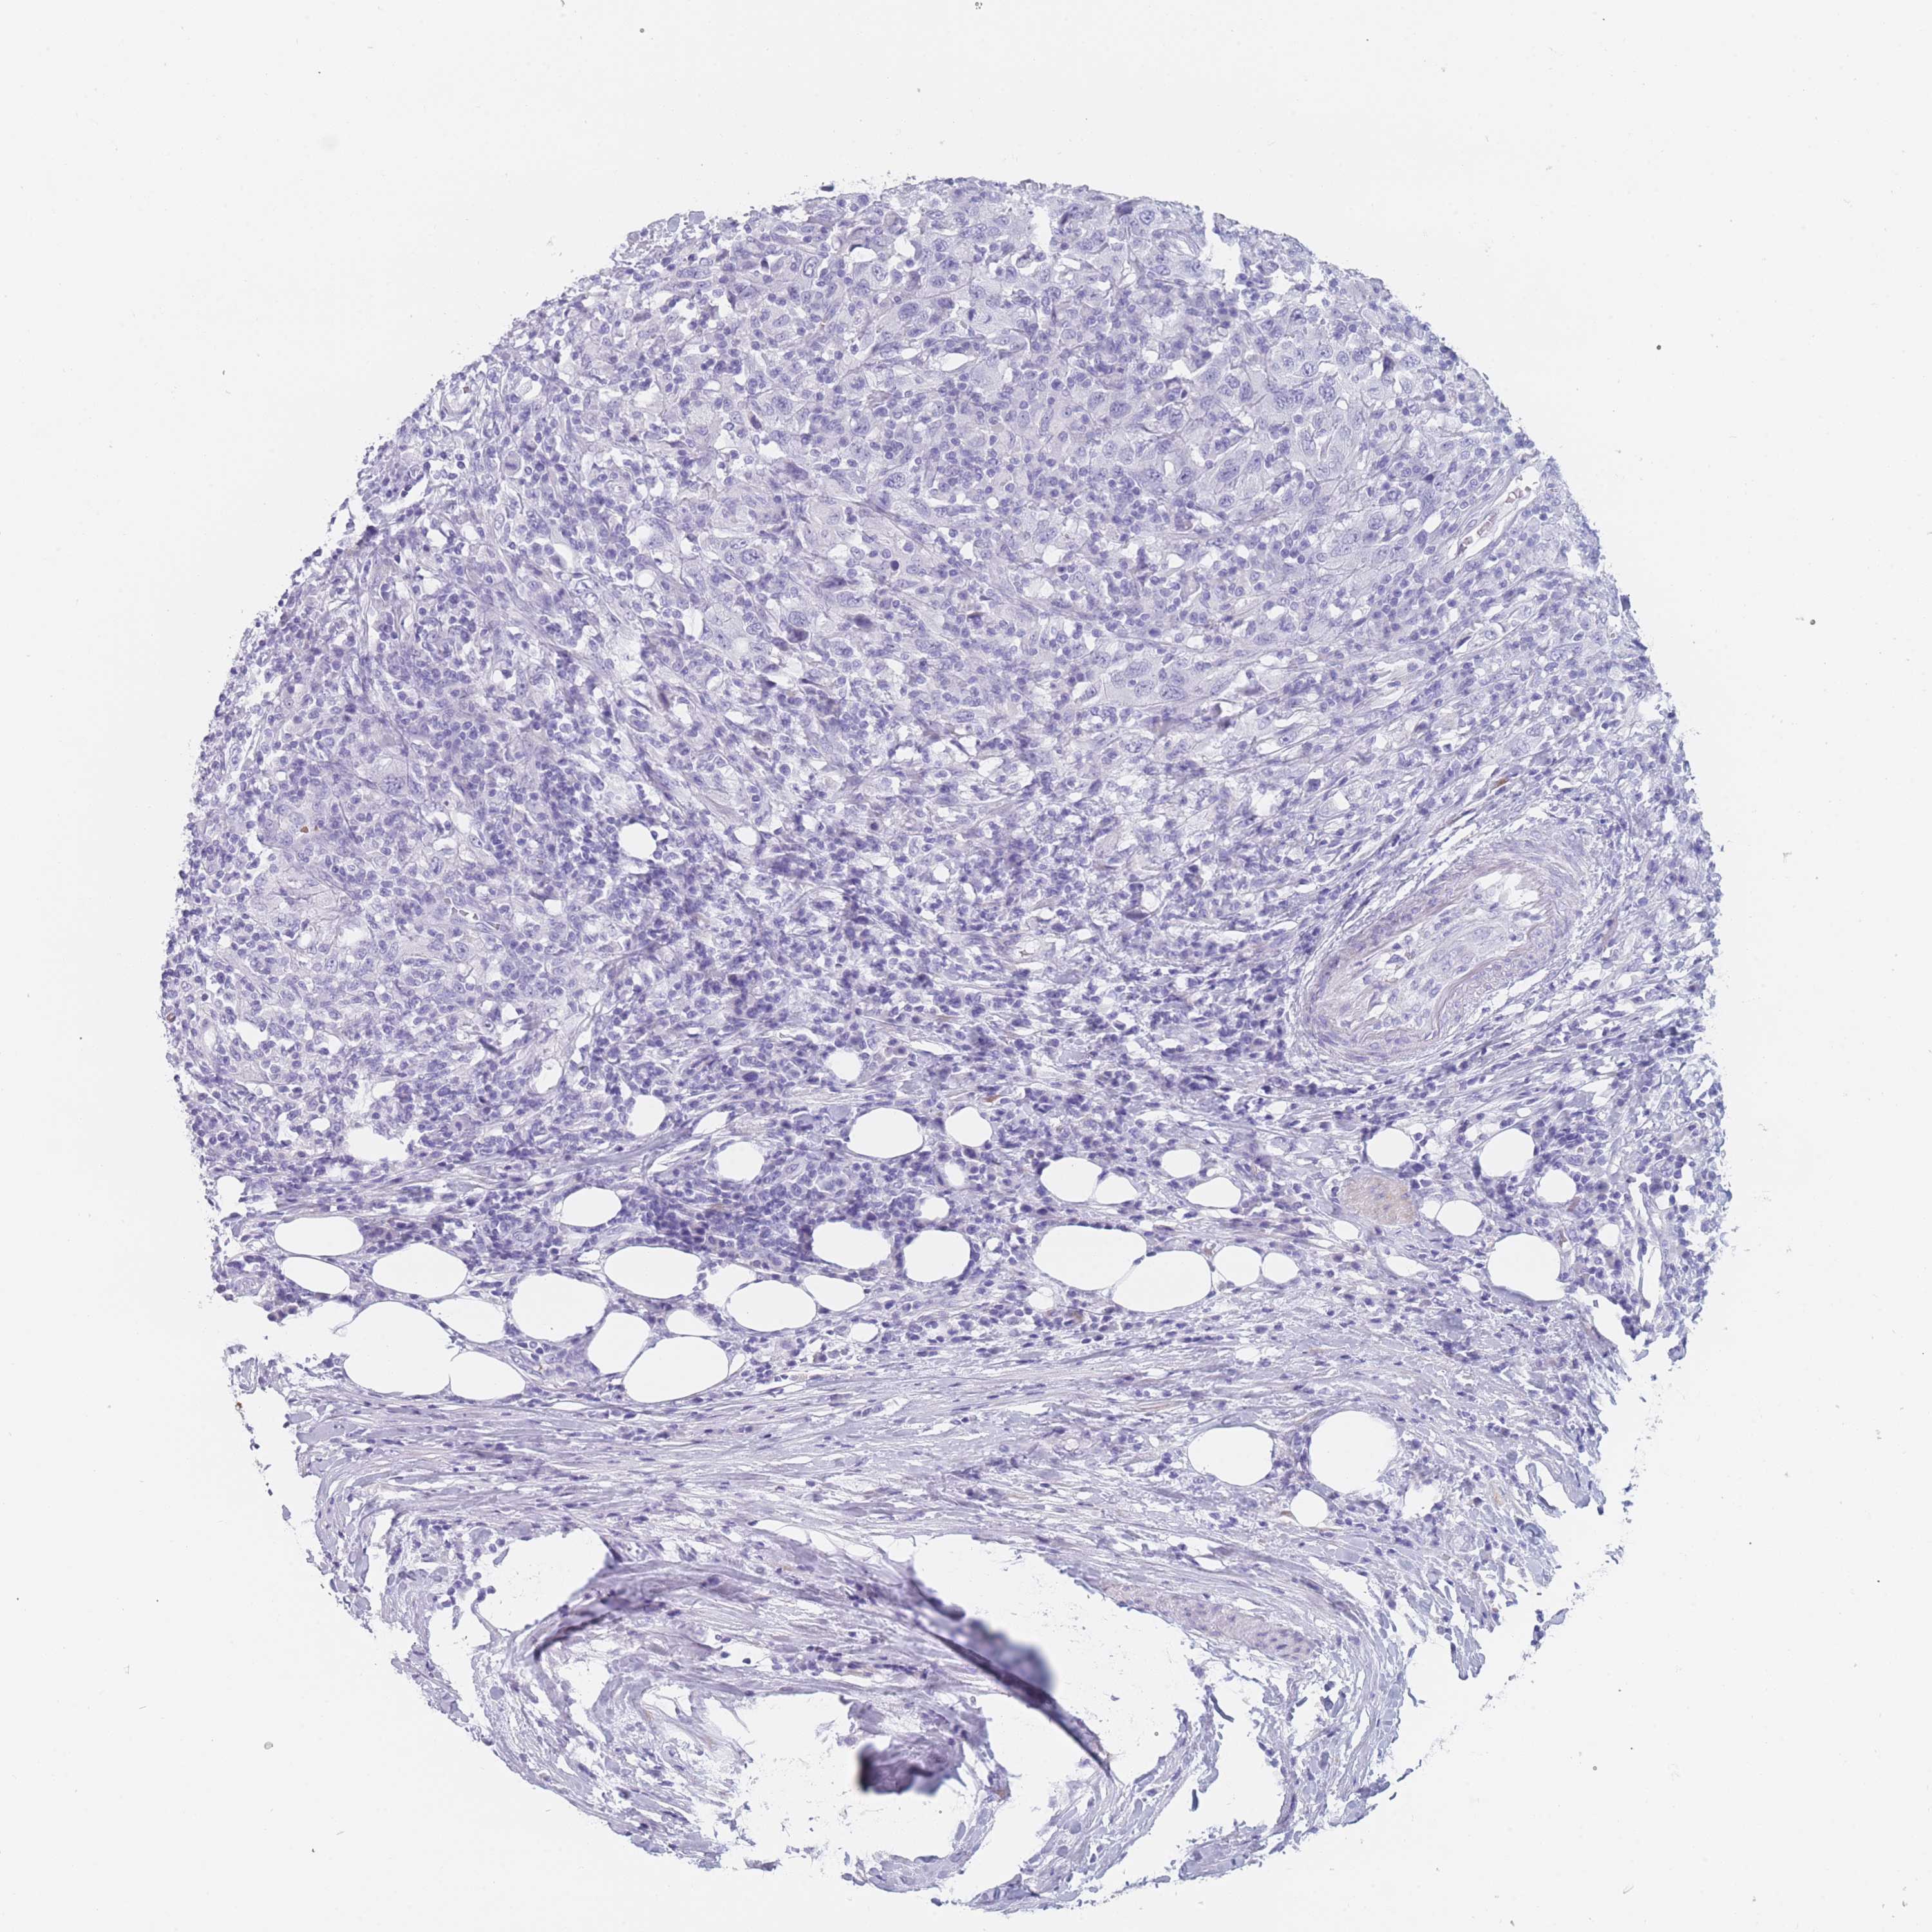

UROTHELIAL CANCER - Protein expressioni

A mouse-over function shows sample information and annotation data. Click on an image to view it in a full screen mode. Samples can be filtered based on level of antibody staining by selecting one or several of the following categories: high, medium, low and not detected. The assay and annotation is described here.

Note that samples used for immunohistochemistry by the Human Protein Atlas do not correspond to samples in the TCGA dataset.

Antibody stainingi

Antibody staining in the annotated cell types in the current human tissue is reported as not detected, low, medium, or high, based on conventional immunohistochemistry profiling in selected tissues. This score is based on the combination of the staining intensity and fraction of stained cells.

Each image is clickable and will lead to virtual microscopy that enables deeper exploration of all samples and also displays staining intensity scores, fraction scores and subcellular localization as well as patient and tissue information for each sample.

Antibody HPA046711

Staining

High

Medium

Low

Not detected

Intensity

Strong

Moderate

Weak

Negative

Quantity

>75%

75%-25%

<25%

None

Location

Nuclear

Cytoplasmic/membranous

Cytoplasmic/membranous,nuclear

Urothelial carcinoma, Low grade

Urothelial carcinoma, High grade

Urothelial carcinoma, NOS